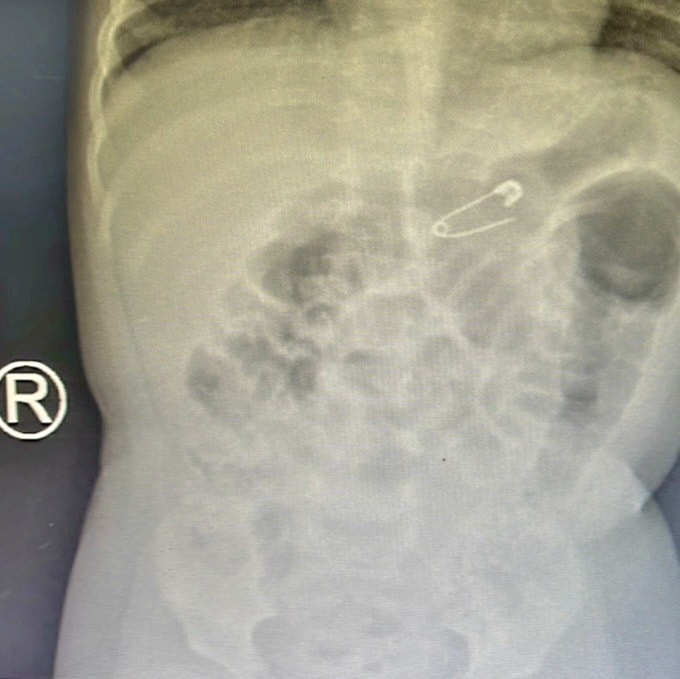

Tại bệnh viện, kết quả chụp X-quang ngực thẳng nghiêng phát hiện dị vật hình kim băng 1,5 x 1cm mắc tại khu vực dạ dày của bé.

Dị vật hình kim băng 1,5 x 1cm mắc tại khu vực dạ dày của bé.